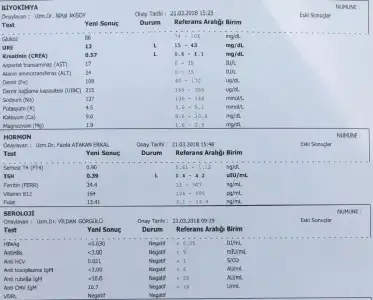

11+2 deyız gecen hafta tsh testı yaptırmıstım sonucları aldık sizce normal mi fikri olan var mı

11+2 deyız gecen hafta tsh testı yaptırmıstım sonucları aldık sizce normal mi fikri olan var mı

11+2 deyız gecen hafta tsh testı yaptırmıstım sonucları aldık sizce normal mi fikri olan var mı

birde bebeğimin cinsiyet tahminini yapabilecek var mı :)